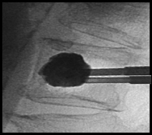

手術は全身麻酔をして行います。ベッドにうつぶせに寝た状態で背中を2か所(1cm程度)切開し、手術にはレントゲンの透視装置を使用します。

- 背中から針を刺入し、骨折した椎体への細い経路を作ります。そこへ小さな風船のついた器具を入れます。(図1)

- 椎体の中に入れた風船を徐々に膨らませ、つぶれた骨を持ち上げて、できるだけ骨折前の形に戻します。(図2)

- 風船を抜くと、椎体内に空洞ができます。その空間を満たすように、 骨セメントを充填します。(図3)

- 手術は1時間程度で終わり、骨セメントは手術中に固まります。(図4)

骨セメントは約1時間で固まりますが、安全のために2時間程度、ベッド上で安静をとってもらっています。以降は歩行など自由にしてもらいます。また治療の後、一時的に針を刺した部分が痛むことがありますが、通常2-3日で良くなります。